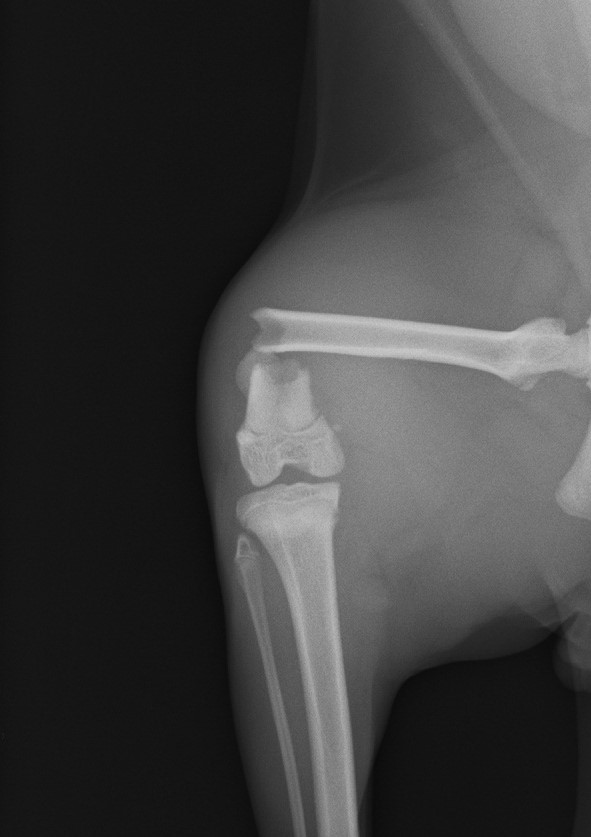

高所からの落下など骨端部骨折は少なくありません。端の手術のため難易度が高くなります。

ダブルプレートによる強固な内固定ではピンニングと比べると、早期に歩行が可能になります